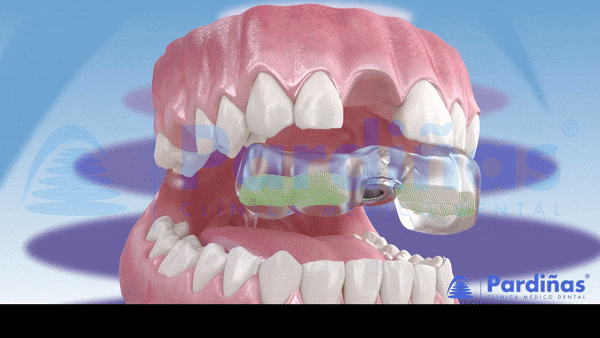

Hướng dẫn phẫu thuật in 3d (Nguồn: Image3dconversion)

Hướng dẫn phẫu thuật kỹ thuật số cuối cùng được sử dụng

sau khi in và trải qua quá trình xử lý bổ sung trông như sau.

Tại vị trí đặt implant đã được khoan một lỗ nên tất cả

những gì bạn phải làm là đặt implant theo đúng lỗ.

Hướng dẫn phẫu thuật kỹ thuật số Implant

Đặt trụ implant bằng máng phẫu thuật (Nguồn: Pardinas)

Nhờ có hướng dẫn phẫu thuật, có thể thực hiện phẫu thuật bằng cách khoan

một lỗ tối thiểu tại vị trí đặt implant mà không cần phải rạch trên nướu của bệnh nhân.

Không chỉ rút ngắn thời gian phẫu thuật mà quy trình phẫu thuật cũng trở nên đơn giản hơn.